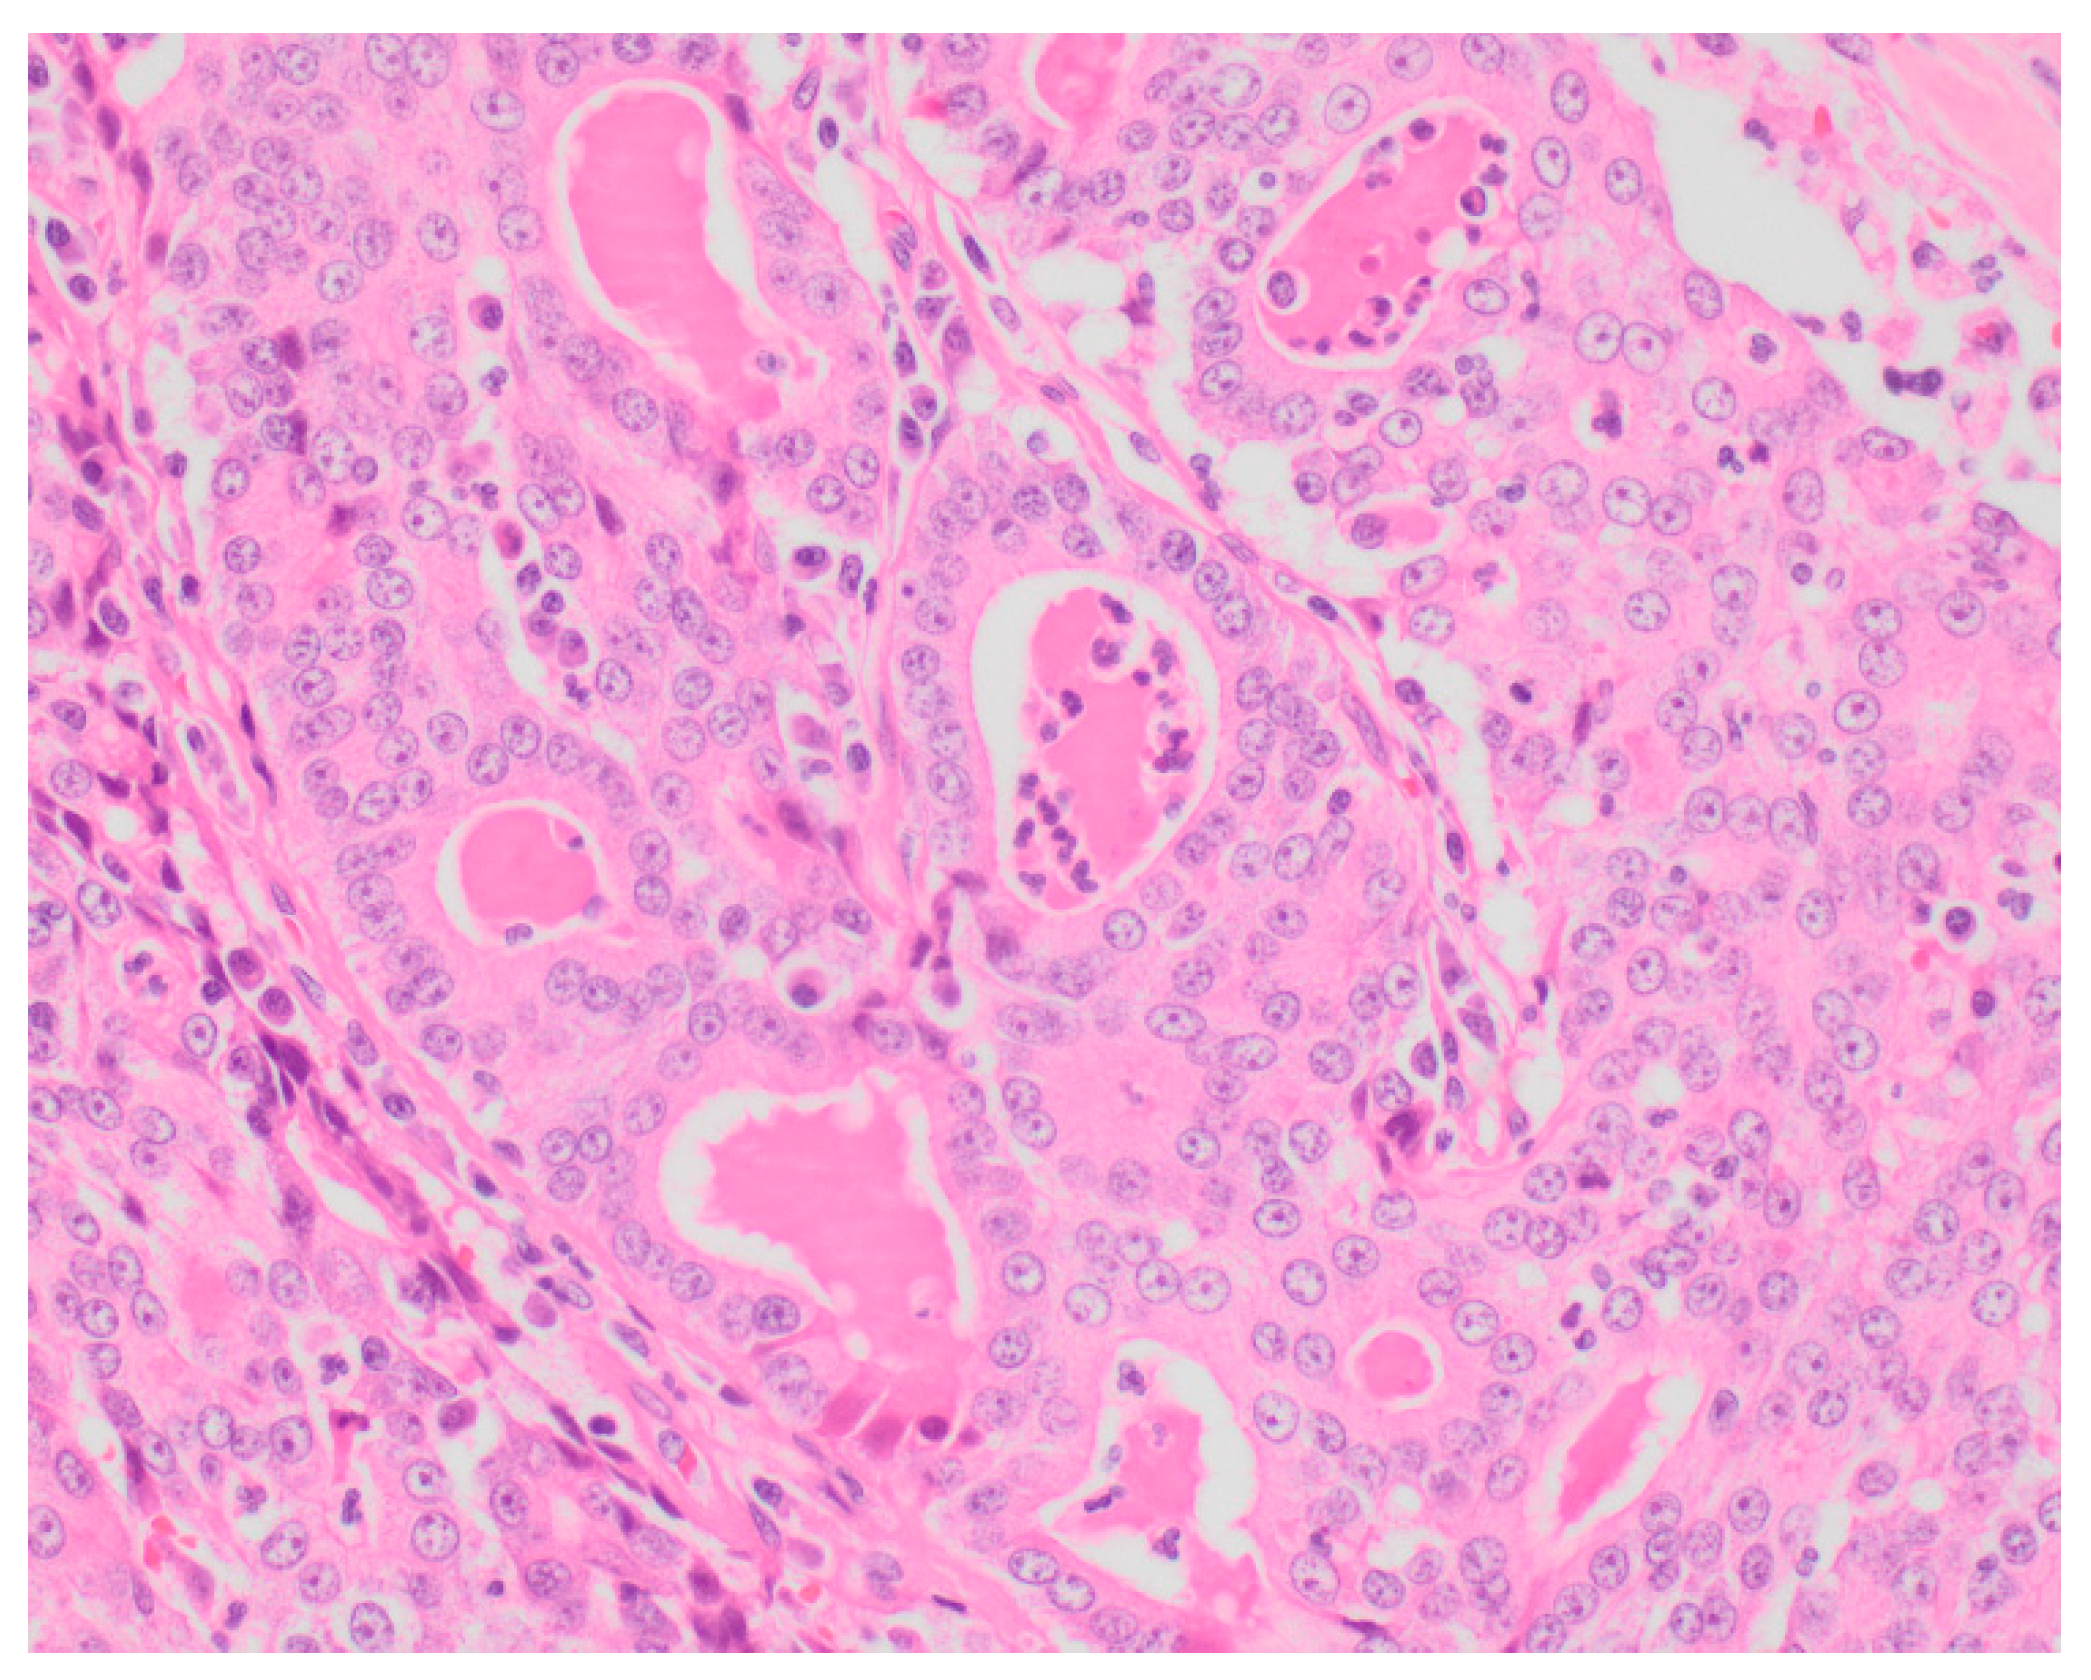

Sixty-five (87.8%) of the tumors examined histologically were classified as malignant, while 9 (12.2%) were classified as benign. All MGTs histologically identified as malignant included at least three cellular or nuclear criteria of malignancy (Figure 1 and Figure 2). Histological evidence of peri-tumoral (n = 6) and lymphatic (n = 4) invasion was identified in 10 malignant tumors, while randomly distributed areas of necrosis within the neoplasm were observed in 16 malignant tumors.

Figure 2. Tubular carcinoma (Grade III), mammary gland, canine (high power). Highly pleomorphic neoplastic cells exhibiting multiple cellular and nuclear criteria of malignancy.